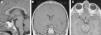

La histiocitosis de células de Langerhans (HCL) es una enfermedad rara caracterizada por la acumulación en los tejidos de células dendríticas anómalas similares a las células de Langerhans. La presentación clínica varía desde la aparición de una lesión ósea única hasta la afectación multisistémica. La implicación del sistema nervioso central (SNC), manifestada como diabetes insípida secundaria a afectación hipofisaria, es conocida desde la descripción original de la enfermedad. En la actualidad, se diferencian 2 tipos de lesiones del SNC: las lesiones seudotumorales, con infiltración por las células de Langerhans, cuya manifestación más frecuente es la infiltración hipofisaria, y otras, de más reciente descripción, las lesiones neurodegenerativas del SNC, asociadas a deterioro neurológico, que constituyen una complicación de la enfermedad de causa discutida. Nuestro objetivo es describir las manifestaciones radiológicas de la HCL en el SNC en los pacientes pediátricos.

Langerhans cell histiocytosis (LCH) is a rare disease characterized by the accumulation within tissues of anomalous dendritic cells similar to Langerhans cells. The clinical presentation varies, ranging from the appearance of a single bone lesion to multisystemic involvement. Central nervous system (CNS) involvement, manifesting as diabetes insipidus secondary to pituitary involvement, has been known since the original description of the disease. Two types of CNS lesions are currently differentiated. The first, pseudotumoral lesions with infiltration by Langerhans cells, most commonly manifests as pituitary infiltration. The second, described more recently, consists of neurodegenerative lesions of the CNS associated with neurologic deterioration. This second type of lesion constitutes a complication of the disease; however, there is no consensus about the cause of this complication. Our objective was to describe the radiologic manifestations of LCH in the CNS in pediatric patients.